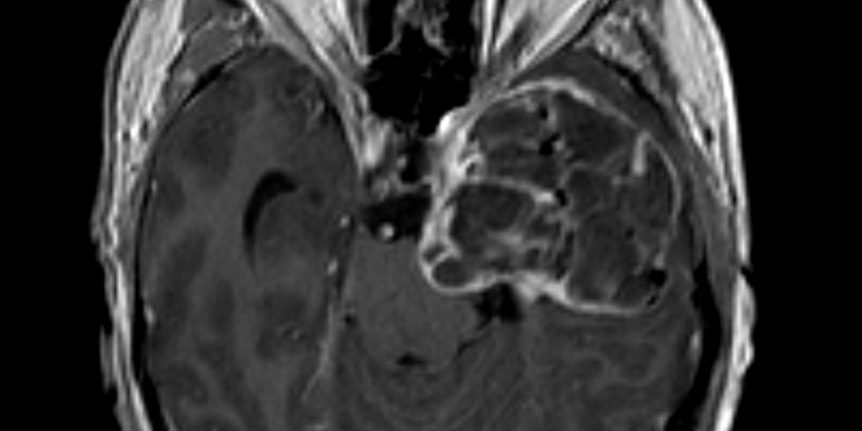

Η μαγνητική τομογραφία εγκεφάλου ανέδειξε εκτεταμένη χωροκατακτητική εξεργασία του μέσου κρανιακού βόθρου, πιθανότατα υποτροπή του δερμοειδούς όγκου για τον οποίο είχε χειρουργηθεί ο ασθενής το 1991.

Ασθενής άνδρας, 66 ετών με ιστορικό χειρουργηθείσας εξεργασίας (δερμοειδές) το 1991. Στους μετεγχειρητικούς ελέγχους αναδείχθηκε υποτροπή και προοδευτική άυξηση της χωροκατακτητικής εξεργασίας αριστερά κροταφικά.